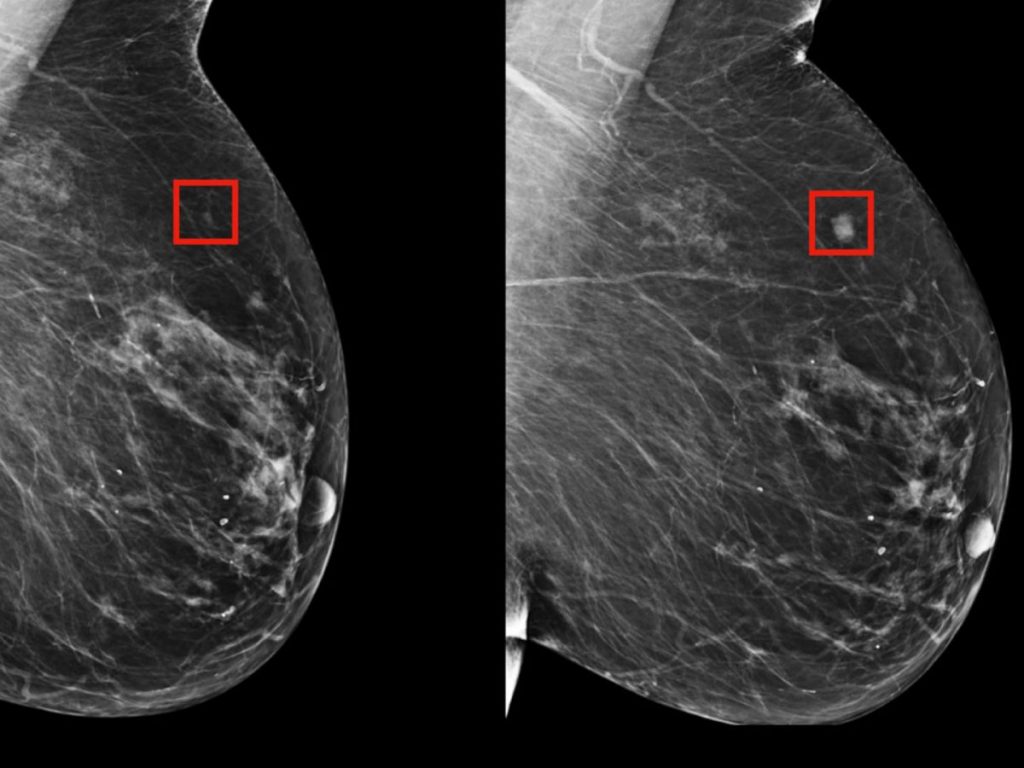

Někde mezi šedými pixely mamografu — tam, kde lékař vidí jen rovnoměrnou strukturu tkáně — algoritmus nachází mikroskopický vzor. Ne nádor. Ne stín. Dokonce ani náznak patologie. Spíš statistický šepot, který se opakuje na tisících podobných snímků žen, jež o několik let později uslyšely děsivou diagnózu.

Stroj „nevidí“ rakovinu. Rozpoznává predispozici, zašifrovanou v rozložení hustot, textur a šumu. V tom, co lidské oko považuje za náhodu.

Na tomto principu stojí systém Mirai z Massachusetts Institute of Technology — model schopný odhadnout riziko rakoviny prsu až pět let dopředu z běžné mamografie. Bez krevních testů. Bez genetiky. Bez příznaků.

Každý mamografický snímek není jen obrázek. Je to matice čísel. Tisíce hodnot hustoty tkáně uspořádaných v prostoru.

Algoritmus se učí na stovkách tisíc snímků, u nichž je známý vývoj pacientek v následujících letech. Nehledá „nádor“. Hledá vzorce, které statisticky často předcházejí jeho vzniku.

To, co člověk vnímá jako šum, model chápe jako předzvěst.